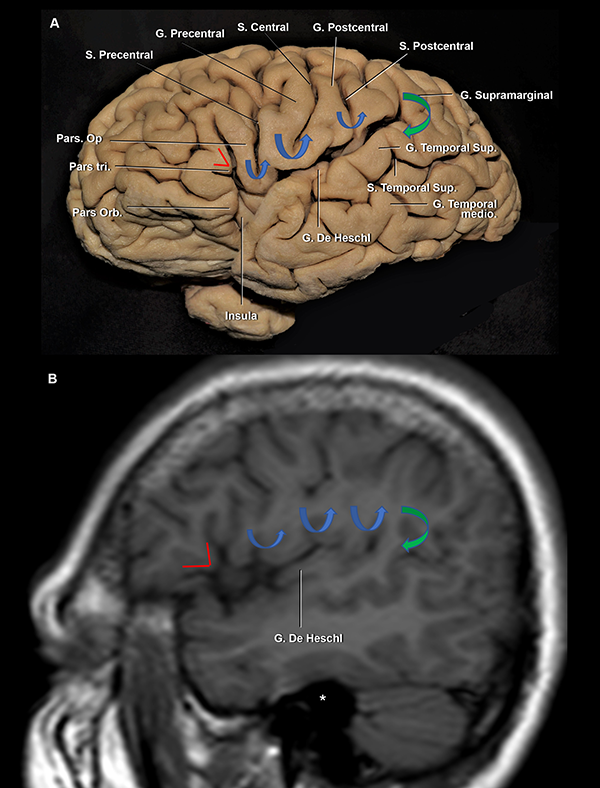

Figura 3: Vista lateral de un hemisferio cerebral derecho. Estrella azul: punto silviano anterior. El limen insular, el genu de la ACM y, frecuentemente, la bifurcación de la ACM se localiza medial e inmediatamente anterior a este punto. Estrella naranja: punto rolándico inferior. Estrella roja: punto silviano posterior. La ínsula se proyecta lateralmente desde el ramo horizontal a la parte más anterior del giro supramarginal; y desde la parte más superior de la pars triangularis y el ramo ascendente hasta el surco temporal superior. Línea punteada verde, azul y roja: proyección de los surcos semicirculares insulares anterior, superior e inferior, respectivamente. S: surco; G: giro; Ram: ramo; Sup: superior; Med: medio; Asc: ascendente; Desc: descendente; Term: terminal; Orb: orbitalis, Tri: triangularis; Op: opercularis; Hor: horizontal.

Figura 5: A. Vista lateral de un hemisferio cerebral izquierdo. B. RMN, secuencia T1, corte sagital. La pars triangularis tiene forma de “V” (líneas rojas). Luego, encontramos 3 giro con forma de “U” (flechas azules), de anterior a posterior: 1) pars opercularis; 2) giro subcentral; y 3) la conexión entre los giros postcentral y supramarginal. Finalmente, la flecha verde marca la conexión con forma de “C” entre los giros supramarginal y temporal superior. Se observa al giro de Heschl enfrentado al postcentral. Ambos se encuentran en el mismo plano coronal que el CAE. Asterisco: proyección medial del CAE. S: surco; G: giro; Sup: superior; inf: inferior.

El lóbulo central se localiza posterior a la pars opercularis y se compone de los giros pre y postcentral.18,22 El puente neural que conecta dichos giros en el extremo inferior del surco central es el giro subcentral, también denominado pli de passage frontoparietal inferior de Broca u opérculo rolándico (Figura 4A y 5A).22,23 El giro precentral se recuesta superficialmente sobre el tercio medio de la corteza insular y el cuerpo de los ventrículos laterales. El surco central corre en una dirección paralela al surco central de la ínsula. Está reportado en la literatura que hasta en el 84% de los casos, el surco no se extiende hasta contactar la FS, en consonancia con nuestros hallazgos.12,18 El giro postcentral se ubica superficial al tercio posterior de la ínsula (Figura 4A y B).

Se dice que la angiografía digital (AD) muestra el esqueleto en el cual las estructuras neurales son organizadas. Su comprensión profunda es esencial para el planeamiento quirúrgico. La corteza insular está cubierta e irrigada por el segmento M2 (Figura 7A). Consecuentemente, en una AD, el lóbulo insular se localiza inmediatamente medial a M2 (Figura 11A y B).21 Los límites anterior, superior e inferior del lóbulo insular también pueden ser reconocidos en la AD. Los puntos de cambio de dirección, o loops, de la ACM distal al genu marcan la transición M2/M3 y se localizan en el surco limitante insular anterior y superior (Figura 7A y B). El tronco inferior de M2 cursa a lo largo del surco limitante inferior (Figura 7A). El punto donde el ramo más posterior de M2 cambia de dirección y se aleja de la ínsula dirigiéndose hacia el opérculo temporal (transición M2/M3) es el punto M o silviano, en la AD (Figura 12B, 11A, 11B).12,14,15,26,30 El punto M es un reparo imagenológico de gran utilidad. Este punto indica el extremo posterior insular y la parte más posteromedial del giro de Heschl. Así también, en una incidencia anteroposterior, el punto M indica la posición de, de lateral a medial, el brazo posterior de la cápsula interna, el pulvinar del tálamo y el atrio (Figura 12B).

El triángulo silviano6,14,15 es un reparo encontrado en la incidencia lateral estricta en un AD. Sus bordes son dibujados por los loops M2 anterior y superiormente, y por el tronco inferior cursando por el surco limitante inferior insular, inferiormente. Este triángulo tiene un ángulo superoanterior recto, marcando el punto insular anterior. El contenido de este triángulo es el lóbulo insular y el core central. Inmediatamente por fuera del triángulo se encuentran los ventrículos laterales (Figura 11B).

La bifurcación carotídea se relaciona con el ápex uncal y el segmento proximal de M1 se relaciona inferiormente con el segmento anterior del uncus. Más aún, el genu de M1 se localiza en el limen insular, por lo tanto, en una AD, marca el borde anterior de la ínsula. La pars triangularis está ubicada unos milímetros distales al genu de M1. Dado que el giro precentral cubre el tercio medio de la ínsula, se puede inferir que el giro precentral en una AD se localiza en el punto medio del triángulo silviano. Finalmente, el extremo posterior del lóbulo insular se localiza en el punto M. Consecuentemente, lesiones vascularizadas localizadas en el genu de M1, son encontradas unos pocos milímetros proximales a la pars triangularis, cerca del polo insular; lesiones localizadas inmediatamente distal al genu, se relacionan superficialmente con la punta de la pars triangularis; y aquellas posicionadas en el punto medio entre el genu y el punto M, son mediales al giro precentral (Figura 11A y B).15

Las ramas M3 que cursan sobre el plano polar son más curvilíneas que aquellas del plano temporal, a causa de la superficie relativamente más plana de la primera. El primer segmento recto de M3 identifica el extremo lateral del giro de Heschl (Figura 11A).15 Entonces, el giro de Heschl está enmarcado entre el punto M y el primer tramo recto de M3 (Figura 7B).